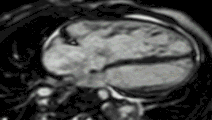

Late gadolinium enhancement

Gadolinium-based contrast agents are administered intravenously and delayed imaging is performed at least 10 minutes later to achieve optimum contrast between normal and infarcted myocardium. An inversion recovery (IR) sequence is used to null the signal from normal myocardium. Myocardial viability can be assessed by the degree of transmural enhancement. Cardiomyopathic, inflammatory and infiltrative diseases may also have distinctive patterns of non-ischemic LGE.[22][23]